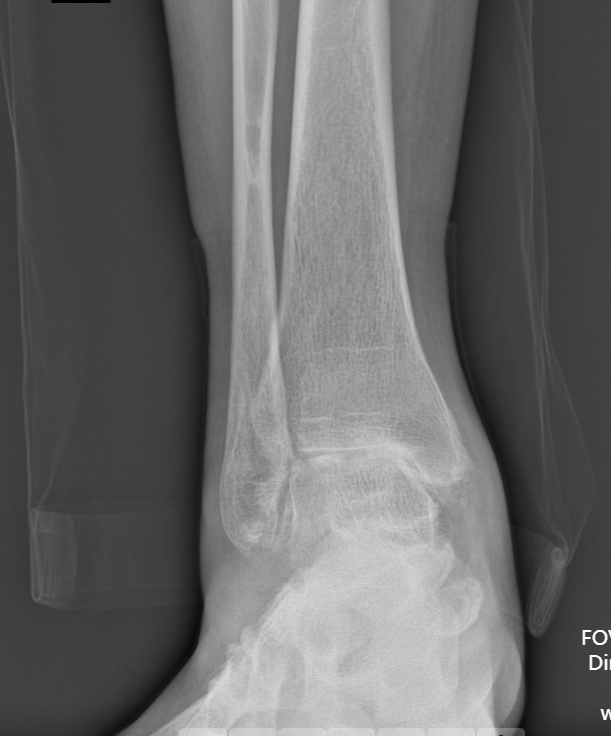

术前踝关节正位X线

武勇主任团队给他做了3D打印导板辅助下人工全踝关节置换术。

这种手术适合踝关节病严重的患者,通过替换病变的关节结构,能帮着缓解疼痛、恢复关节活动,让老人日常走路更自在些。